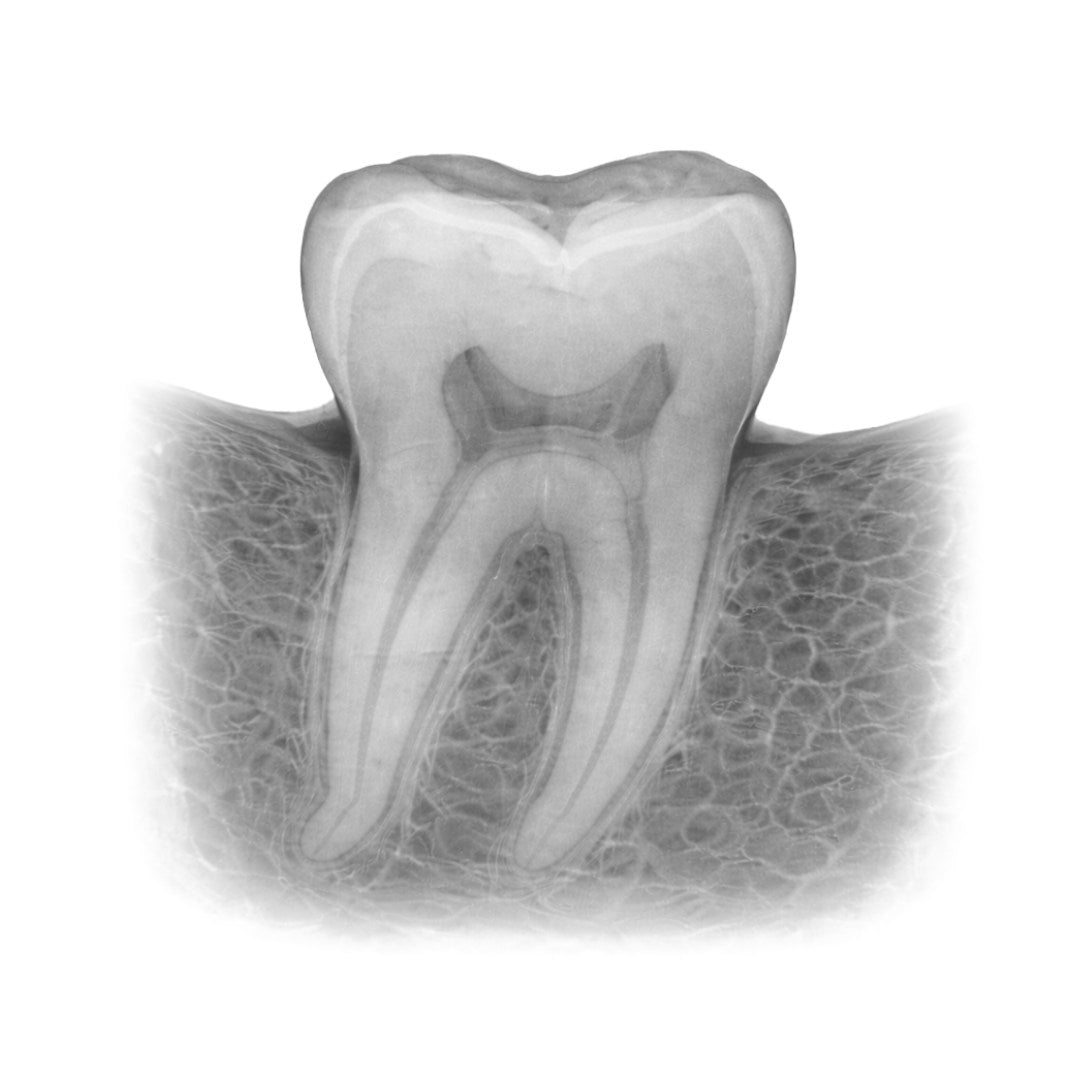

Røntgenbilder gir verdifulle innblikk i tannhelsen din. Ved å bruke røntgen kan tannlegen identifisere tidlige tegn på karies, tannråte, infeksjoner, betennelser og andre potensielle problemer som kan gå ubemerket hen. Det gjør det lettere å sette i gang tiltak tidlig, slik at små problemer ikke utvikler seg til store og kostbare behandlinger.

Røntgenbildene kan også brukes til å overvåke fremdriften i behandlinger som tannregulering, implantater eller rotfylling. Ved å ha tilgang til historiske røntgenbilder kan tannlegen vurdere endringer over tid, og tilpasse behandlingen etter behov.

Digitale røntgenbilder er essensielt for presis diagnostikk og effektiv behandling. Vi bruker moderne røntgenteknologi som gir svært detaljerte bilder av tenner, tannrøtter, kjeveben og omliggende strukturer. Dette gjør at tannlegen raskt og nøyaktig kan identifisere problemer som karies, betennelser, infeksjoner og andre skjulte tilstander.

Digitale røntgenbilder gir tannlegen innsikt i din munnhelse som ikke er synlig ved vanlig undersøkelse. Disse bildene muliggjør tidlig diagnose, nøyaktig behandling, og forebygging av mer alvorlige problemer. Med minimal stråling og høy presisjon sikrer vi trygghet og gode resultater for din tannhelse.